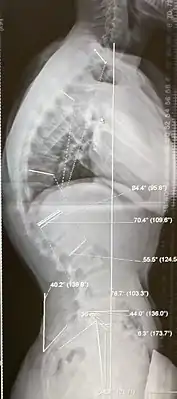

Горб — деформация позвоночника (реже — грудной клетки), характеризующаяся резко выраженным кифозом. Упоминания о горбах встречаются ещё у Гиппократа.

Возникновение горба является результатом ряда заболеваний или повреждений, наиболее часты — туберкулёзный спондилит, рахит, а также механические травмы позвоночника. Кроме того, риск появления горба возникает вследствие систематического нарушения осанки. Вследствие разрушения патологическим (в случае заболевания) либо механическим процессом (при травме) тел отдельных позвонков происходит их деформация, влекущая за собой, в свою очередь, искривление позвоночника в передне-заднем и боковом направлениях. Одновременно с возникновением горба на позвоночнике происходит деформация и грудной клетки — возникает так называемый рёберный горб, который также может появиться и при боковом искривлении позвоночника. При возникновении горба у детей и в юношеском возрасте деформация может достигнуть большой степени, так как в растущем организме дальнейшее развитие скелета идёт неправильно.